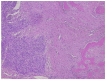

Murine Double Minute Clone 2, located at 12q15, is an oncogene that codes for an oncoprotein of which the association with p53 was discovered 30 years ago. The most important function of MDM2 is to control p53 activity; it is in fact the best documented negative regulator of p53. Mutations of the tumor suppressor gene p53 represent the most frequent genetic change in human cancers. By overexpressing MDM2, cancer cells have another means to block p53. The sarcomas in which MDM2 amplification is a hallmark are well-differentiated liposarcoma/atypical lipomatous tumor, dedifferentiated liposarcoma, intimal sarcoma, and low-grade osteosarcoma. The purpose of this review is to summarize the typical clinical, histopathological, immunohistochemical, and genetic features of these tumors.